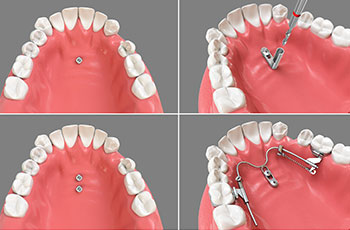

上顎の骨を拡げて、抜歯をしなくても綺麗に歯が並ぶように補助してくれる装置です。

小さいアンカースクリューを顎の骨に埋め込み、これを固定源として歯を動かします。

MSEは、上顎を骨格的に拡げる装置です。上顎天井の骨は左右2つの骨からできており、そのつなぎ目へ右左2本ずつ(計4本)ミニスクリューを埋入します。左右の骨を離す力を加え、離れた隙間に骨が作られることによって、上顎が拡大されます。これにより、抜歯を行わずに歯が綺麗な位置に移動するスペースを確保します。

インプラントアンカー(歯科矯正用アンカースクリュー)は、歯を失った際の補綴で使用されるインプラントと違い。歯科矯正用に開発された小さいアンカースクリューを顎の骨に埋め込み、これを固定源として歯を動かす治療法です。治療期間の短縮や、難症例の歯並び改善にも対応する事が可能になります。

小さなスクリューを上顎骨に埋入し、奥歯(大臼歯)の遠心移動または近心移動を行う装置です。歯の遠心(後方)移動が可能になり、前方へ移動してしまった歯列を元の位置へ戻すことができるようになります。インビザラインでの矯正治療でも応用され、適応が難しかった症例にも対応できるようになります。